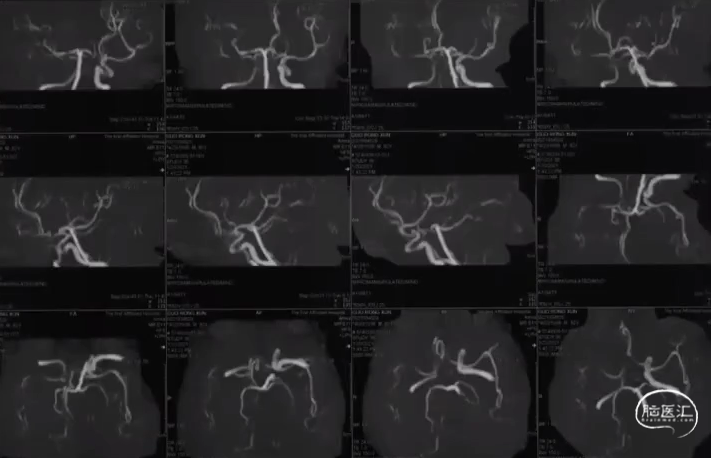

头部MRA

术前DSA R-CCA

术前DSA L-ICA

术前DSA L-VA

术前DSA R-VA